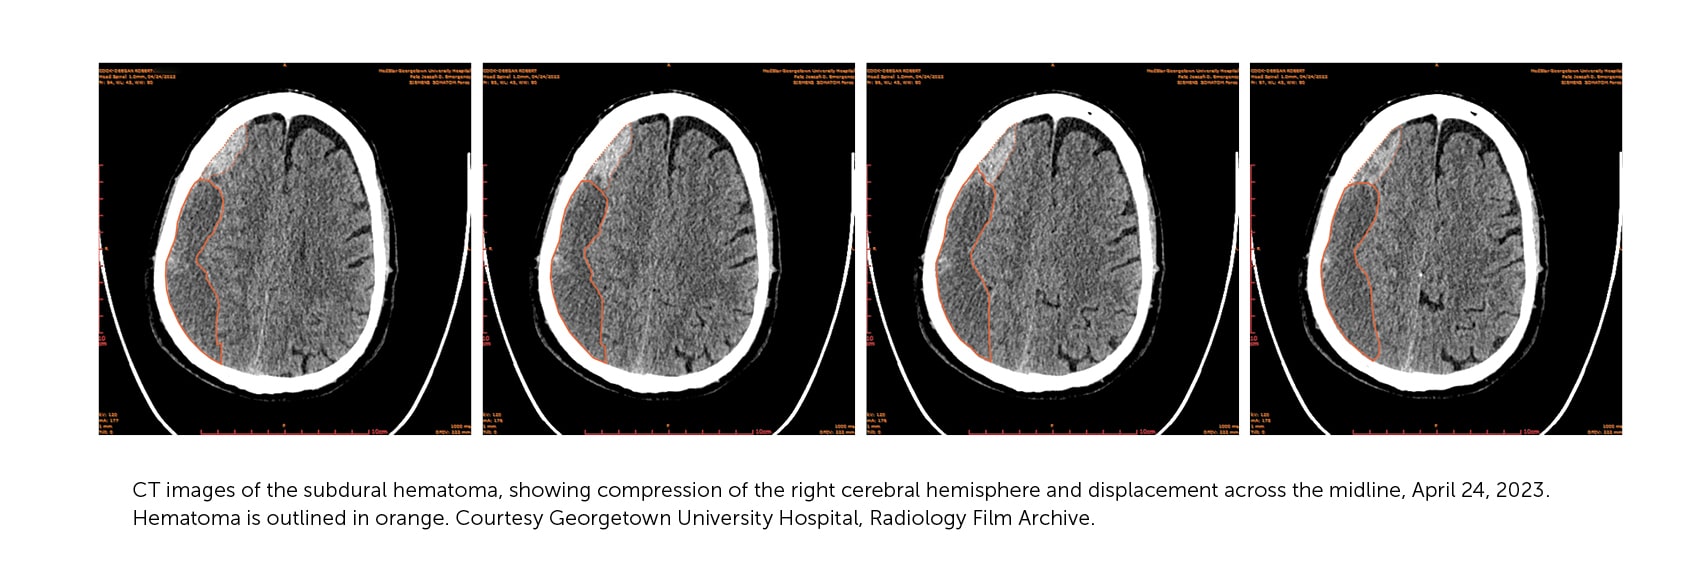

Even at low resolution, the CT image explained a lot. Instead of a stroke, it showed a possibly reversible injury: a chronic subdural hematoma. It was what I had suspected. On the screen, we could see the pool of blood accumulating and mushing my brain across the cranial midline. A blood clot inside your noggin is not a good thing. It takes up precious real estate in a confined space housing a squishy organ. The blood was positioned over the right sensory and motor cortex, causing the weakness and poor coordination of my left side.